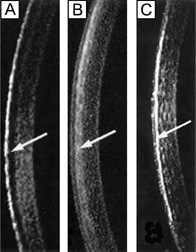

Several surgical procedures have also been developed to permanently alter the curvature of the cornea, thereby reducing nonpathologic refractive errors. The procedures most commonly performed today include laser-assisted in situ keratomileusis (LASIK), photorefractive keratectomy (PRK), and astigmatic keratotomy (AK). LASIK and PRK are surgical techniques that use an excimer laser (193 nm) to ablate the anterior corneal stroma with submicron accuracy and create a new refractive surface. LASIK is different from PRK in that it involves a mechanical or laser created lamellar keratectomy step before the excimer ablation step, which is applied to the underlying residual mid-stromal bed. PRK ablation directly occurs on the surface of the cornea (Bowman's layer and anterior stroma). Both procedures have been used on myopic and hyperopic eyes with up to a mild degree of astigmatism and produce similar visual outcomes. AK is an incisional keratotomy technique that cuts up to 90% depth arcs in the peripheral cornea using a scalpel to reduce astigmatism by flattening the cornea in the visual axis over the area of the cut. AK is usually performed in association with cataract surgery.

Although this review is primarily concerned with healthy, normal corneal endothelium, there are many exogenous stresses that could potentially damage the corneal endothelium. Perhaps the most common interventions that affect the cornea/endothelium include contact lens wear, excimer laser refractive surgery (LASIK, PRK), and intraocular surgery (cataract surgery, refractive IOL surgery, corneal transplantation). Contact lens wear does not appear to cause loss of endothelial cell density, but can acutely induce reversible corneal edema and/or can cause chronic signs of endothelial cell stress (increased polymegathism and decreased pleomorphism).58,114 Contact lens-induced endothelial cell changes are thought to occur because of hypoxia, as they are not observed with more oxygen permeable lenses.114 Excimer-based refractive surgery has only been found to induce acute, transient endothelial cell stress (increased polymegathism and decreased pleomorphism) and loss of barrier function if performed on a cornea with a residual corneal thickness ≤200 μm, presumably because of the shockwave produced by the laser ablation.85 Otherwise, no long-term effects have been linked to laser refractive surgery.85